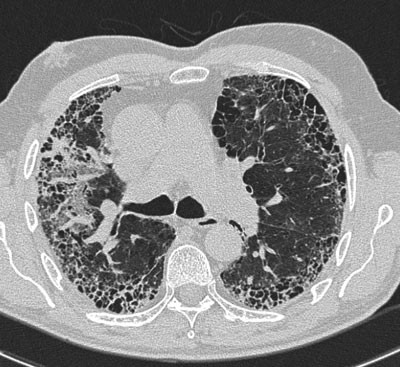

Vi fikk demonstrert CT thorax som nylig var tatt (fig 2), men det viste kun tegn til lungefibrose og ga ikke holdepunkter for verken sarkoidose eller tuberkulose.

Dag seks fikk pasienten høyresidig perifer facialisparese. Cerebral MR viste bare vanlige aldersforandringer, ingen patologisk tilstand med relevans for de aktuelle kliniske symptomer og funn. Pasienten ble malignitetsutredet med CT thorax, abdomen og bekken. Bronkialskylling og sternalmargsaspirasjon ble gjort. På CT-bilder av abdomen ble det bemerket noe fyldige binyrer, men for øvrig var malignitetsutredningen komplett negativ.